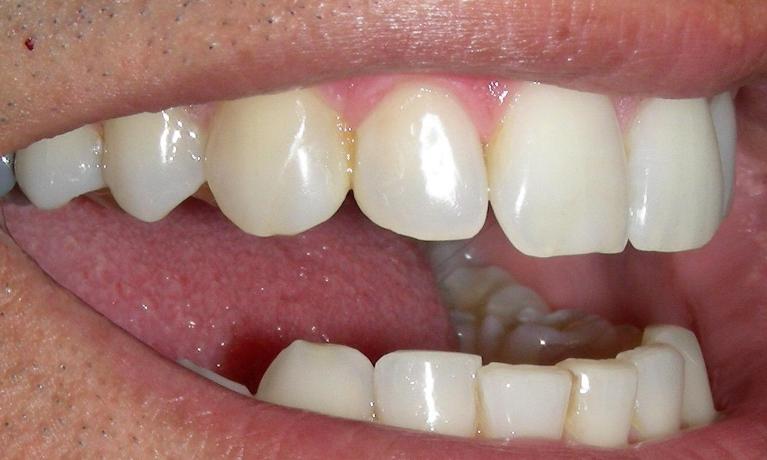

Diagnosis with theLED Transilluminator

The LED Transilluminator is an exciting new instrument that can let us “see into the inside of a tooth by lighting it up like a light bulb.

While in no way does it eliminate the need for dental X-rays, it provides another tool to diagnose decay, cracks and other conditions that might be missed by other methods.